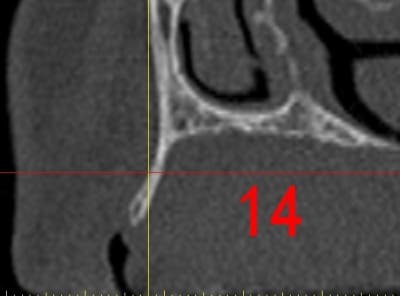

dar14_ygglyj.jpg

La première diapo est un essai pour justifier le concept (os non destiné à une utilisation greffe)

la deuxième est "tapée" dans une tête de femur de mauvais qualité (rejetée)

la troisième et suivante ce sont "les greffons" définitifs.

Pour la mise en forme de la pièce 1 (appui 12) avec la mise en place, le choix de la tête de fémur, et les discussions pour expliquer la mise en forme, il a fallu 1 h environ, qui pourrait etre réduite à une trentaine de minutes, dans un cas comme celui ci, ce qui est déjà énorme pour l'os d'un patient (mise à nu ect...), sans parler des différents stress.